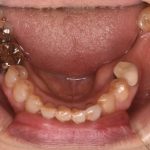

歯が欠けて物が詰まりやすい ダイレクトボンディングによる虫歯治療

治療前 治療後 性別 女性 相談内容 歯が欠けた カウンセリング・診断結果 プラ ...